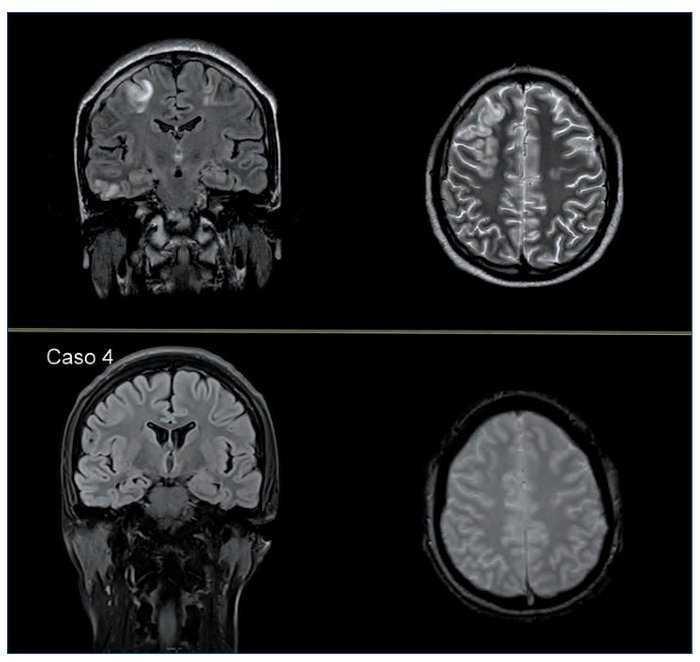

La RMNC mostró una extensa afectación de la sustancia blanca subcortical de la convexidad cerebral, temporal y occipital posterior, sugestiva de SEPR (figura 1 superior).

Figura 1. Superior: En las secuencias T2 y FLAIR se identifica una hiperintensidad cortical y subcortical periférica, de predominio en la convexidad frontal y parietal bilateral, pero también en los lóbulos frontales (de predominio izquierdo), temporal posterior izquierdo, polo occipital posterior derecho, así como en la sustancia blanca profunda (esplenio de cuerpo calloso). Ninguna de las lesiones presenta restricción de la difusión. Inferior: Resolución completa de las múltiples lesiones hiperintensas en FLAIR y secuencia potenciada en T2. No se observan lesiones en el parénquima cerebral, cerebeloso ni en el tronco encefálico. En la secuencia de difusión no se aprecian alteraciones de restricción de difusión.

La RMNC de control a los dos meses mostró resolución completa de las lesiones de la sustancia blanca supratentoriales bihemisféricas visualizadas en el estudio previo, confirmando la sospecha clínica de SEPR (figura 1 inferior).